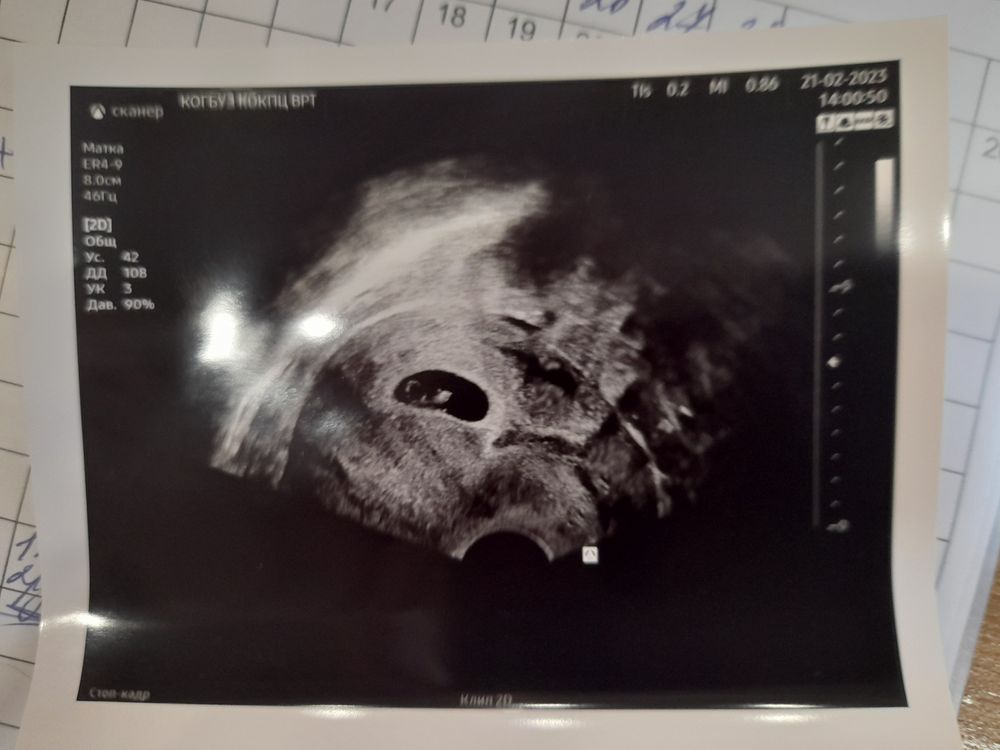

УЗИ на 28 дпп